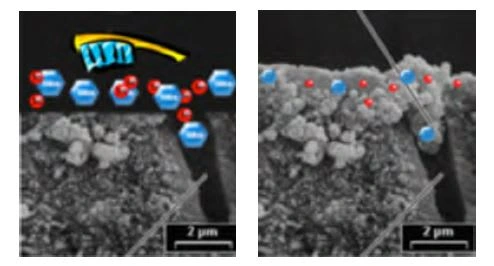

Early treatments using solutions and later gels demonstrated the desensitizing effect of stannous fluoride. The dentinal tubules are occluded by precipitated stannous salts, inhibiting fluid movement within the tubules and thereby preventing nerve stimulation and pain (Figures 13, 14; Miller et al. 1994; Thrash et al. 1995).

Figure 13. Dentinal tubule occlusion: Note the effective occlusion of dentinal tubules with stabilized stannous fluoride dentifrice (SEM x2000)

Figure 14. Pre-and post-brushing SEMs: pre-and post-treatment with open and occluded dentinal tubules Courtesy of Cosmetics & Toiletries

Figure 15. Relative dentinal tubule occlusion for stabilized stannous fluoride dentifrice versus two other anti-hypersensitivity dentifrices after treatment, mechanical agitation, and one minute acid exposure.